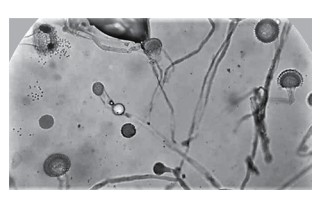

O exame morfológico direto do lavado broncoalveolar de uma paciente internada com broncoespasmo severo revela, em lâmina, o aspecto apresentado na figura a seguir. Assinale alternativa com a melhor opção terapêutica.